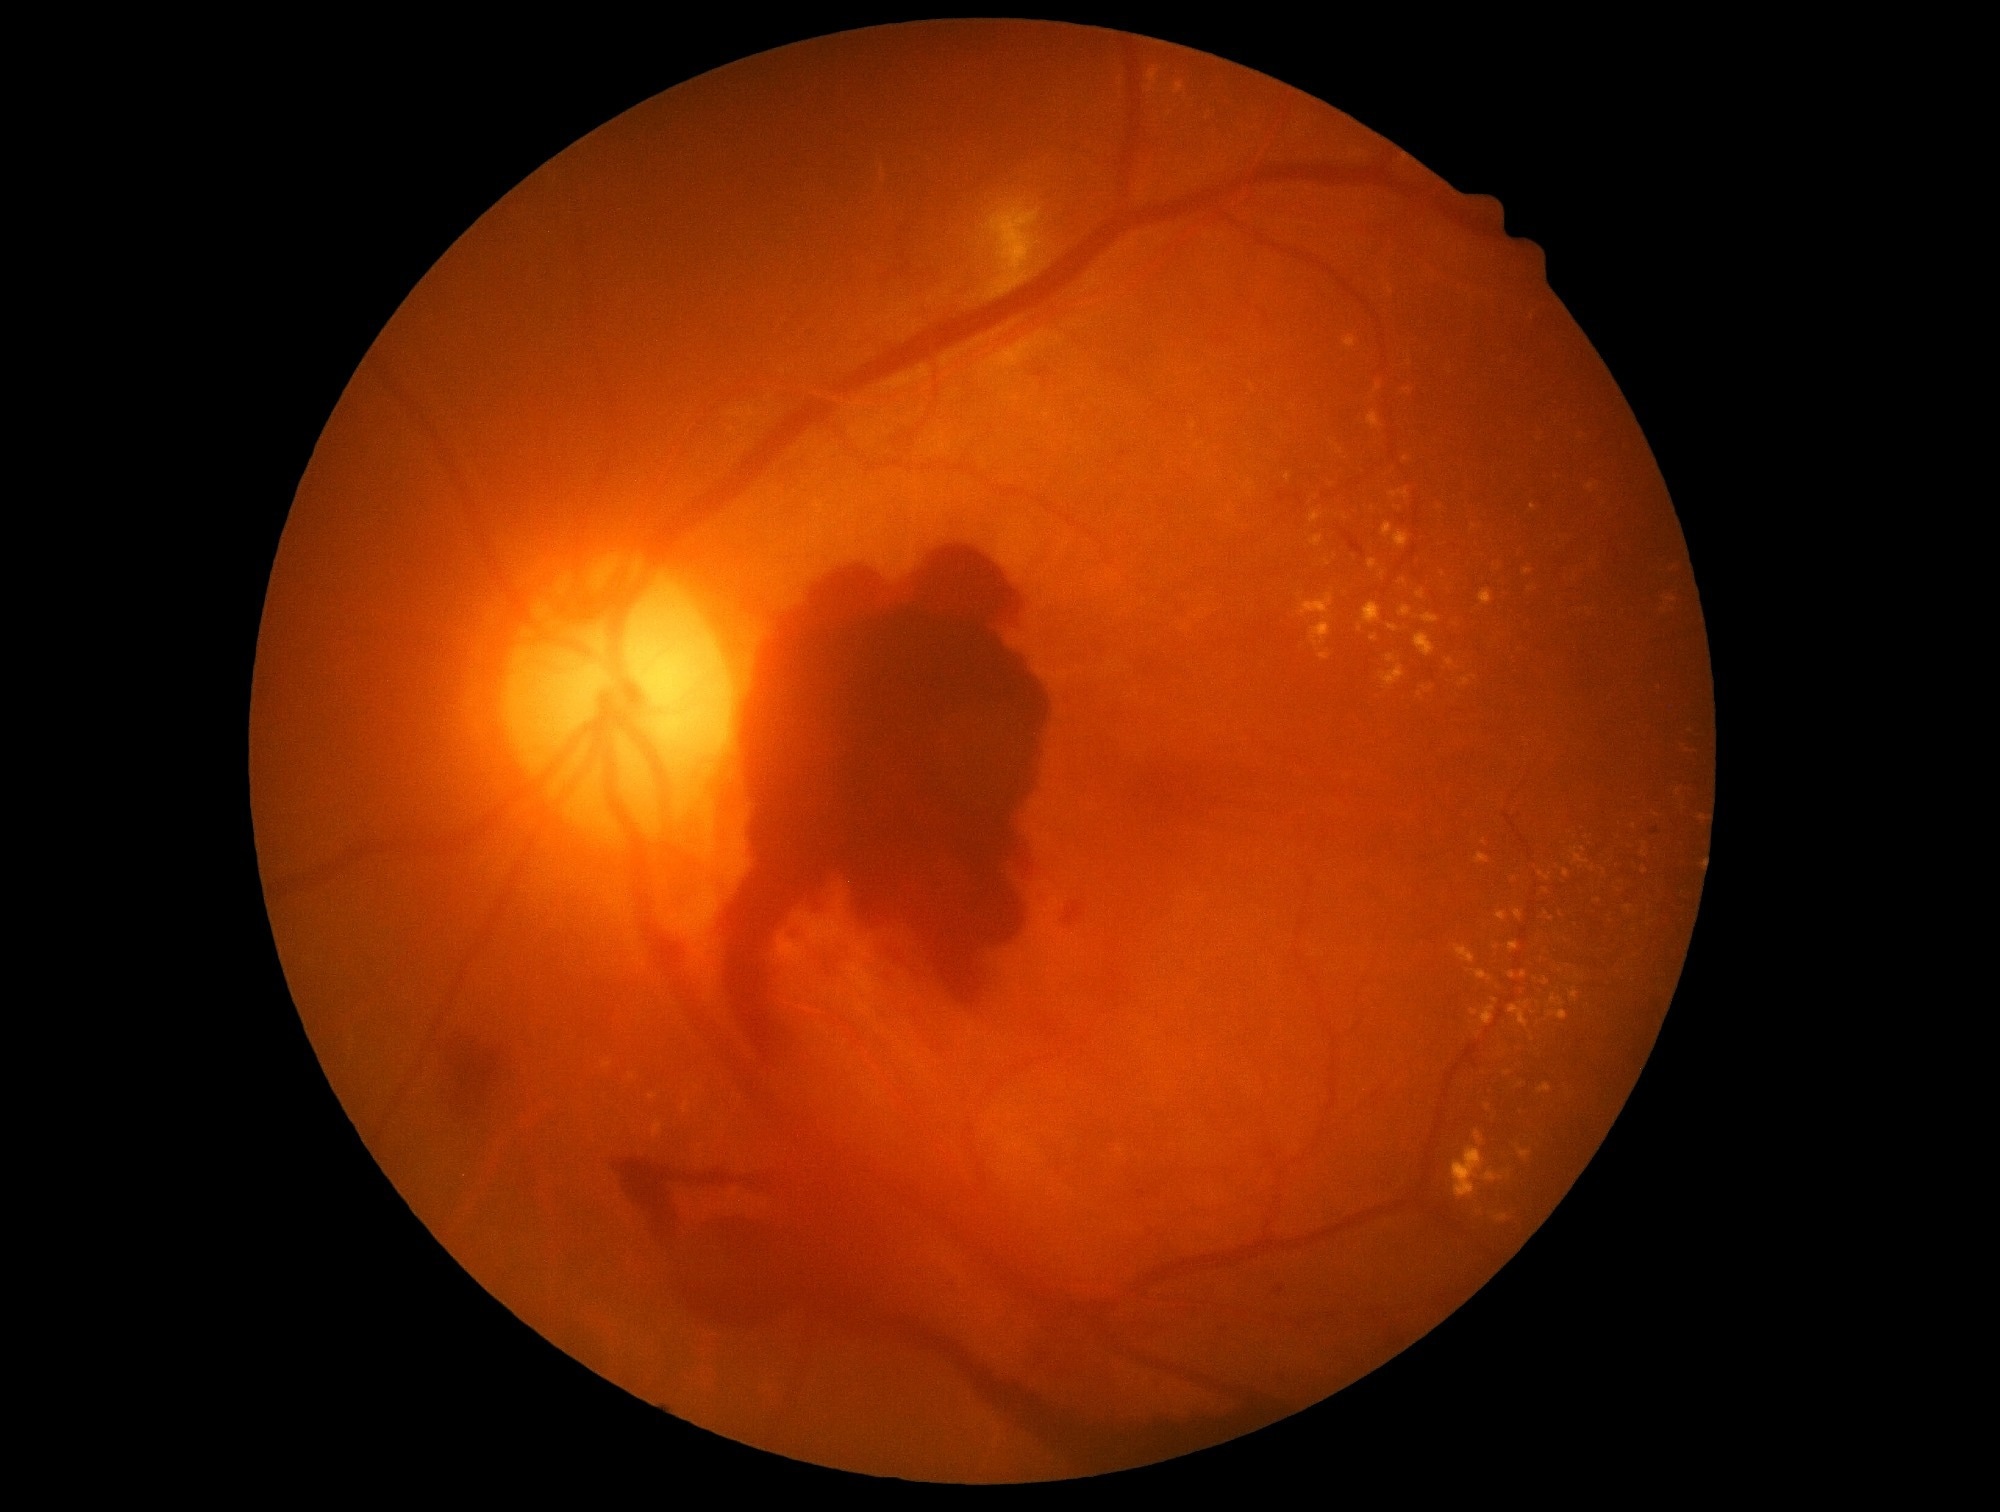

Semaglutide is a widely prescribed antidiabetic medicine that acts as a glucagon-like peptide 1 receptor agonist (GLP-1 RA) for the treatment of type 2 diabetes and obesity. A 2024 study by Hathaway et al., which investigated more than 16,000 patients over a period of six years, raised ocular safety issues related to semaglutide. The study found that the medicine can potentially increase the risk of non-arteritic anterior ischemic optic neuropathy (NAION), a potentially vision-threatening condition.

The comparative analysis revealed that semaglutide use is associated with a significantly higher risk of vision impairment compared to other GLP-1 RAs. Among 11,558 semaglutide-related reports, researchers identified 417 cases specifically related to visual impairment, retinopathy, or ischemic optic neuropathy.

A supplementary analysis focusing specifically on retinopathy found consistent results, with semaglutide showing higher reporting odds compared to other drugs.

Previous clinical trials that investigated the safety and efficacy of semaglutide did not report significant vision complications except for the SUSTAIN-6 trial and a subsequent meta-analysis of 23 trials, which reported a higher risk of diabetic retinopathy complications in patients receiving semaglutide. SUSTAIN-6 documented absolute rates of 3.0% for retinopathy complications with semaglutide versus 1.8% with placebo.